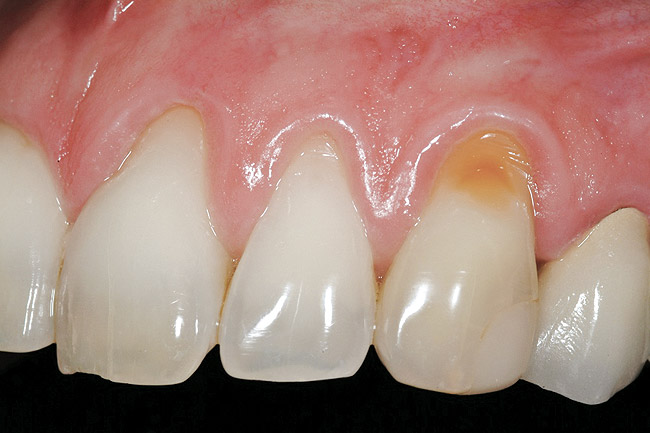

Figure 16  Case Two Preoperative clinical view, maxillary left central incisor.

Figure 16

A 27-year-old non-smoking man presented for esthetic enhancement of the left central incisor, which had a pre-existing full-coverage restoration that required replacement (Figure 16). The patient had begun orthodontic treatment in the mandibular arch to correct a minor occlusal imbalance and required coronal repositioning and soft tissue grafting to correct gingival recession at the facial of the right canine, in addition to correction of the free gingival margin at the facial of the left central incisor, which was asymmetrical to the free gingival margin of tooth No. 8. Additionally, the facial gingival tissues were of a thin biotype, which at the facial surface of the left central incisor allowed for the darkened root surface to be visible through the tissue (Figure 16).

The treatment plan was to accomplish an increased zone of keratinized tissue at tooth No. 6, and increase the thickness of the facial tissue at tooth No. 9, in addition to coronally repositioning the free gingival margin. Complicating this treatment plan was the fact that at the facial surface of tooth No. 9, a biologic width invasion was present due to the prepared margin for the pre-existing restoration being placed too close to the facial alveolar crest of bone (the patient had presented to the periodontist with a provisional restoration in place). Any correction to the area would require movement of the facial margin of the tooth in a coronal fashion to re-establish the appropriate distance from the facial height of bone to the margin of the restoration. Additionally, options were given to the patient for harvesting the soft tissue, using connective tissue from the palate, or the use of an acellular dermal matrix graft, which would nullify harvesting tissue from the palate region.